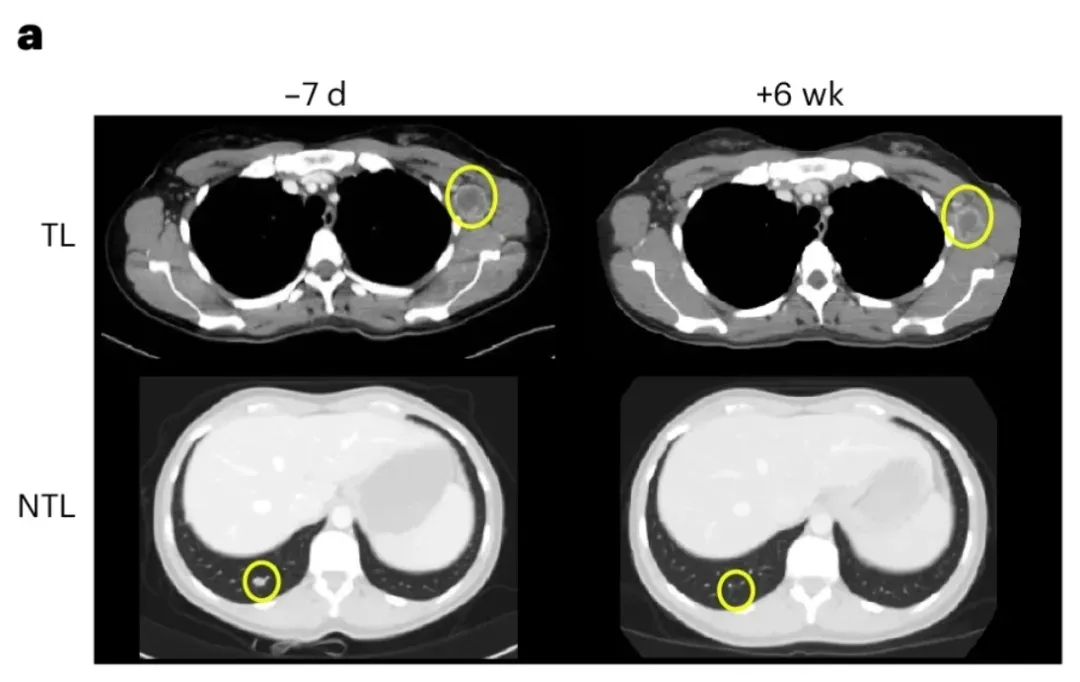

尤为值得关注的是NAC09号患者,其疗效最为突出:治疗6周后CT显示,左腋窝靶病变缩小20%,继发性腋窝淋巴结及毫米级肺转移灶等非靶病变显著缩小(详见下图)。

▼NAC09号患者治疗前后CT扫描对比

▲图源“Nature Medicine”,版权归原作者所有,如无意中侵犯了知识产权,请联系我们删除